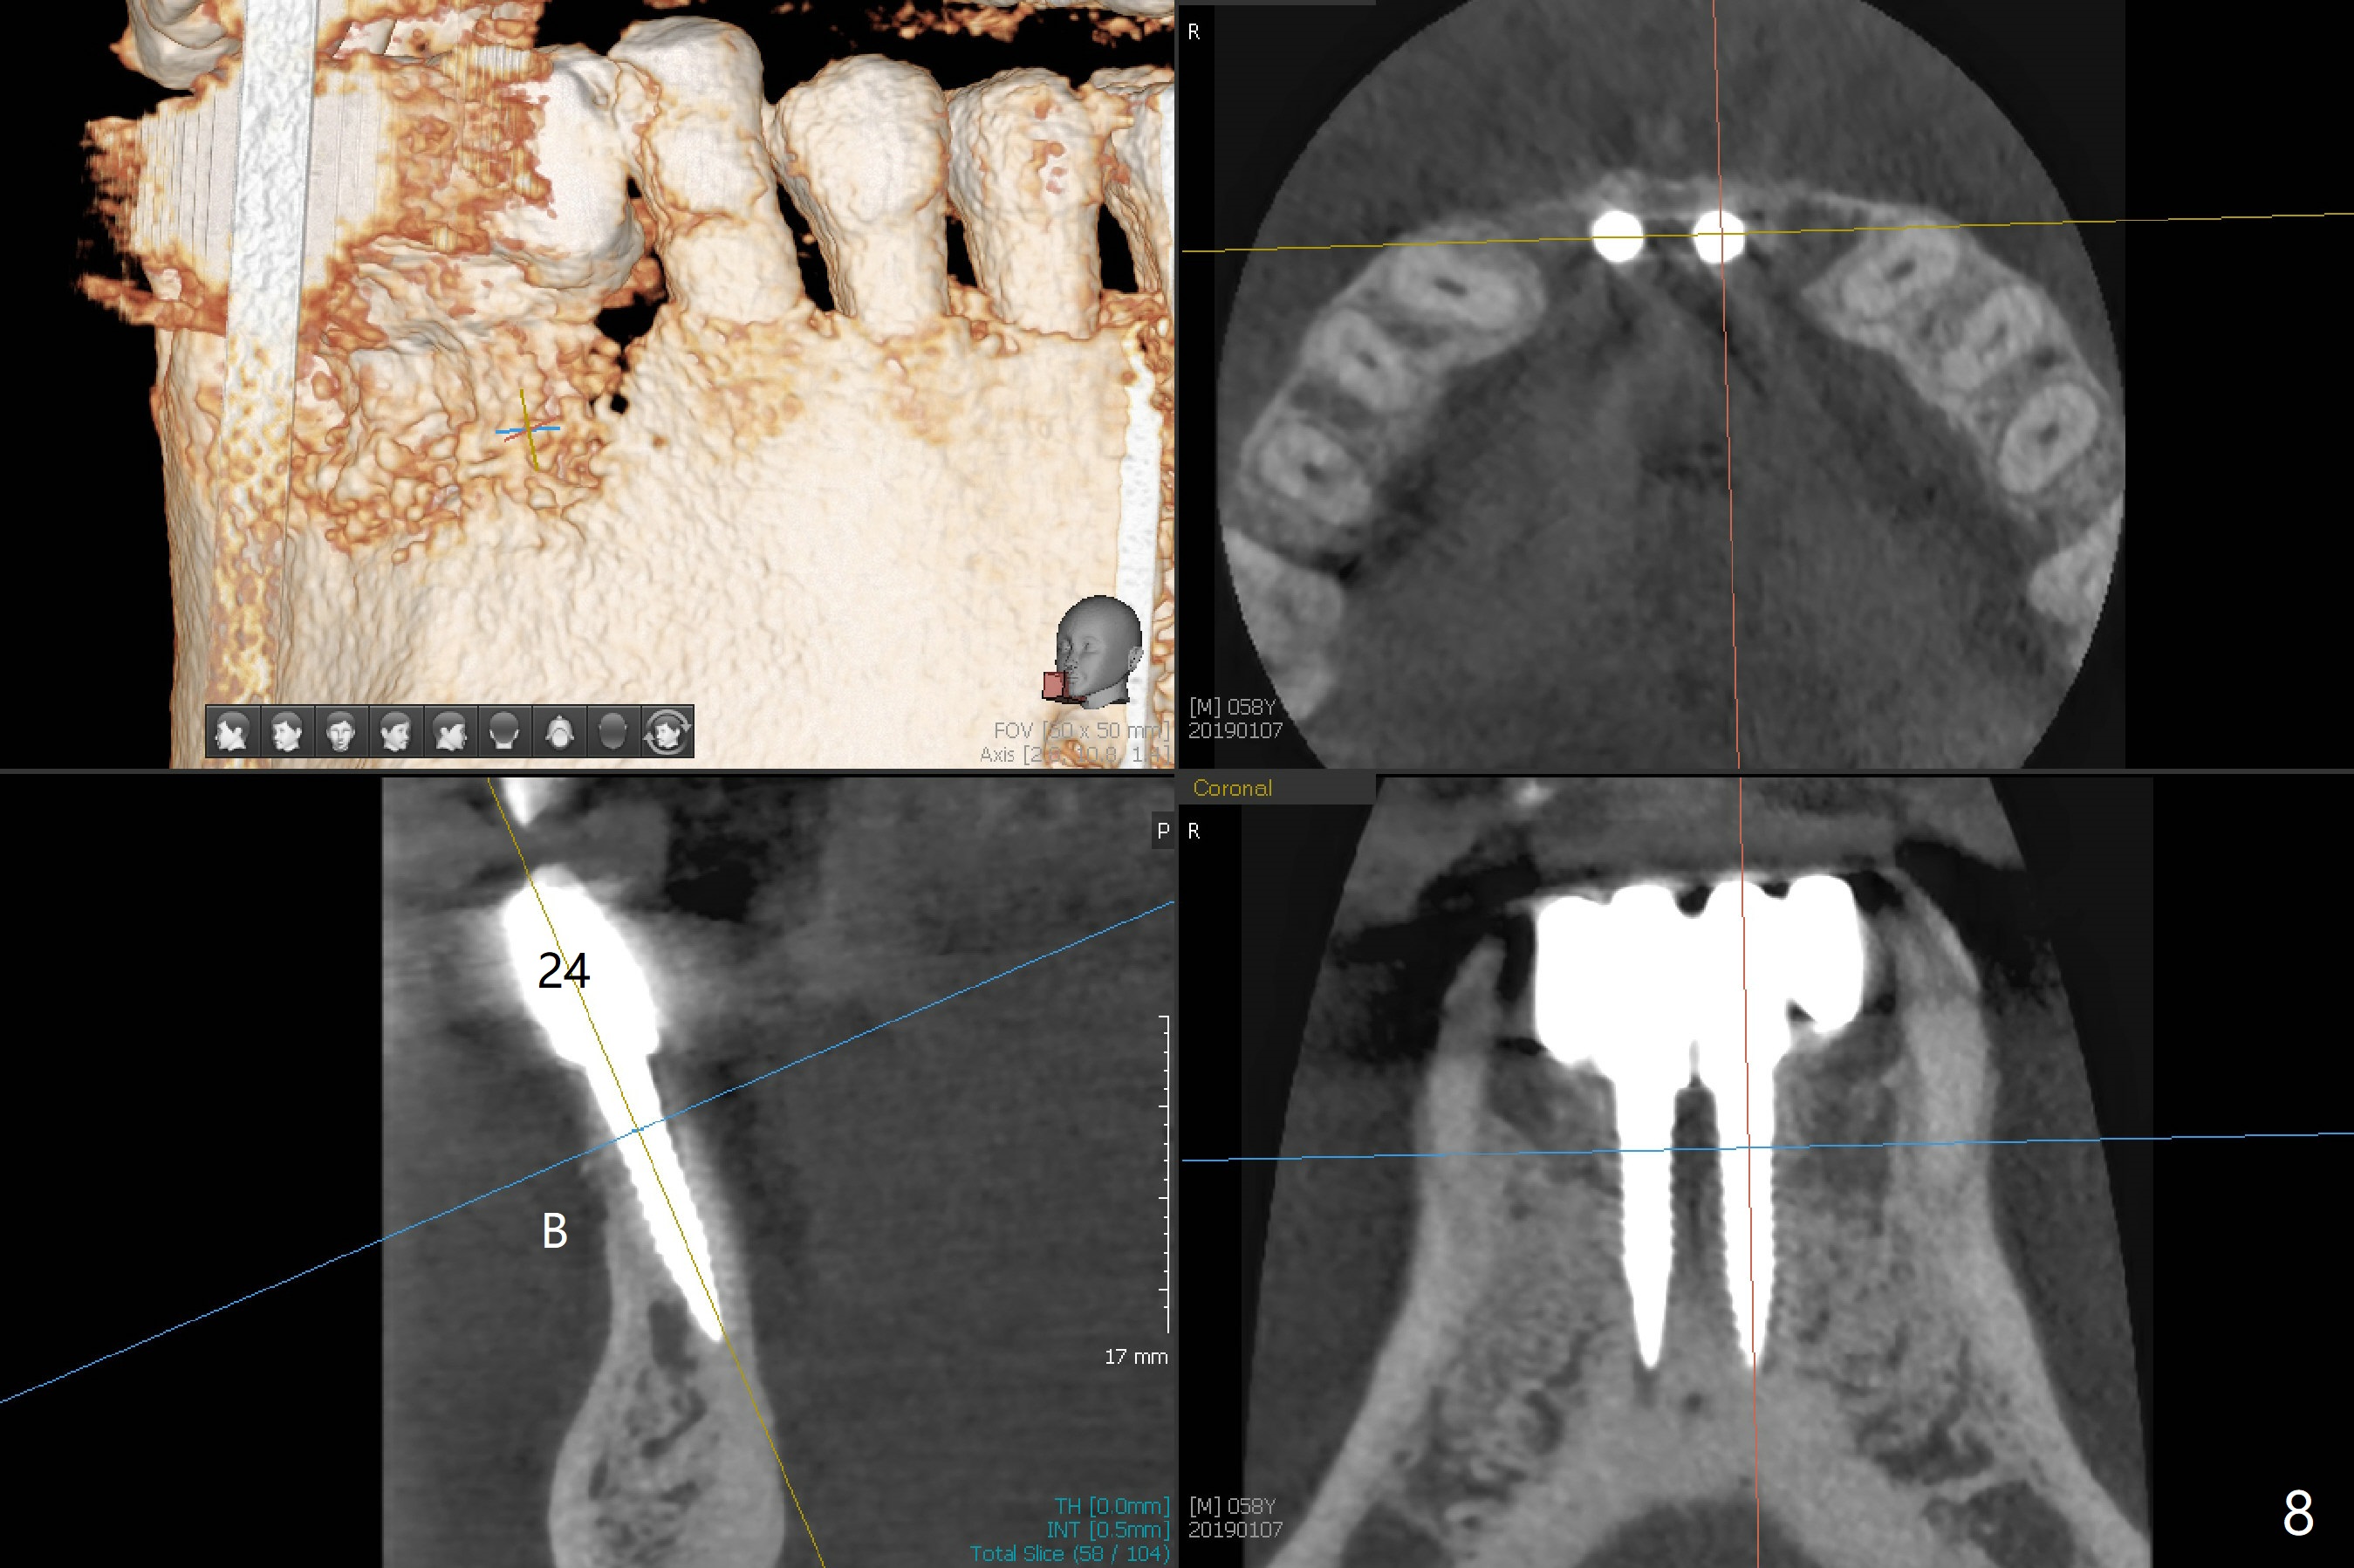

The fenetration found buccal to #25 two months post cementation persists, although asymptomatic, 4 months post cementation. Blood is drawn for PRF. In fact the implants at #24 and 25 are exposed buccal; there is limited amount of the buccal bone (Fig.1 *). After granulation tissue removal, Titanium brush is used to clean the implant threads. Allograft and Osteogen are mixed with PRF liquid to form gel, which is placed over the exposed implant threads. The bone graft is covered with a piece of PRF membrane and a piece of collagen membrane (Fig.2 C). Immediately postop PA (Fig.3) and CBCT (Fig.4) show that the implants have sufficient clearance between them. The implant thread exposure is most likely due to failure to place the implants deep enough and the implants are slightly large relative to the ridge (Fig.5-8). If the bone graft does not heal, new type of 1-piece implants (Fig.9,10 (green) smaller in diameter, 2 or 2.5 mm ) with longer abutment (pink) will be placed subcrestal buccal with guide.